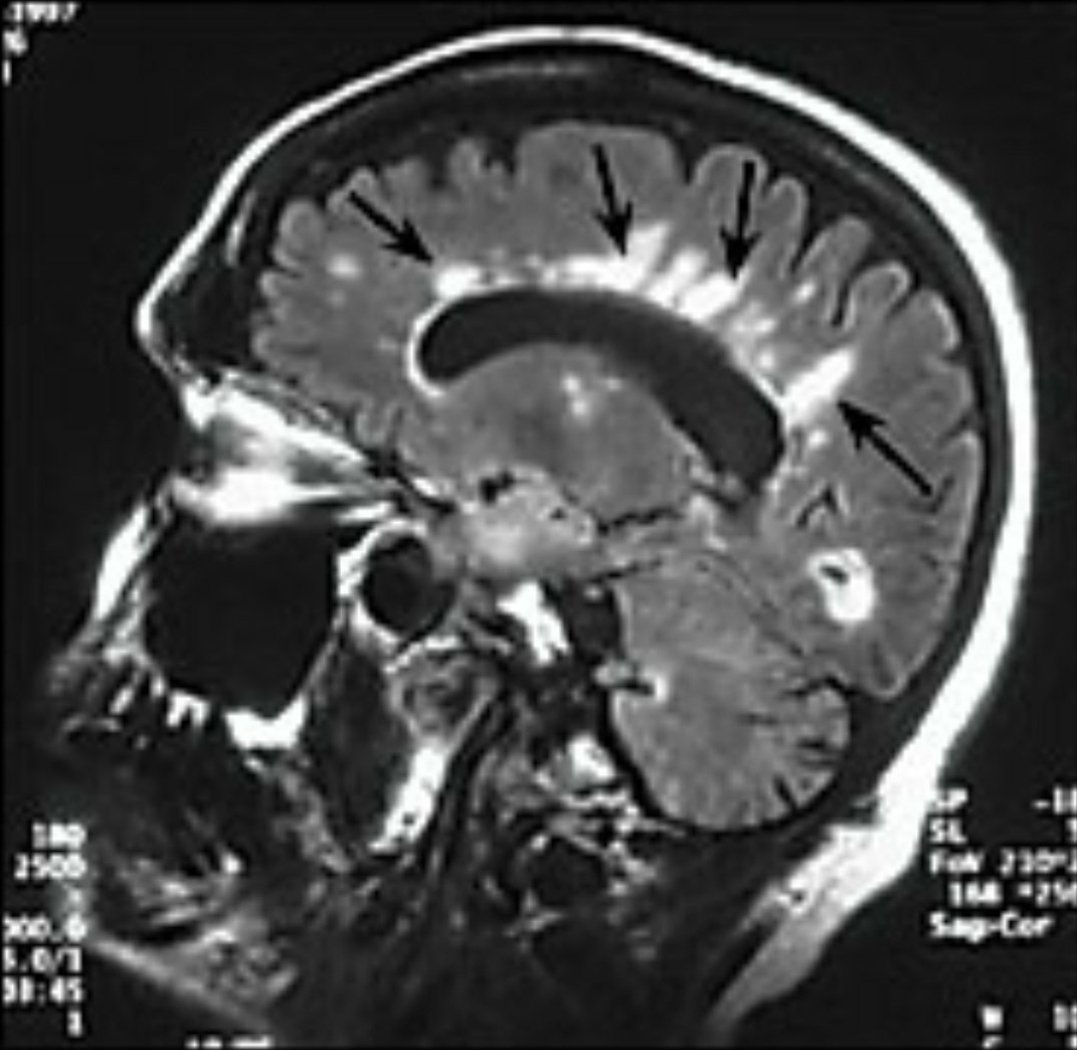

♦️ورنين مغناطيسي للمخ والحبل الشوكي